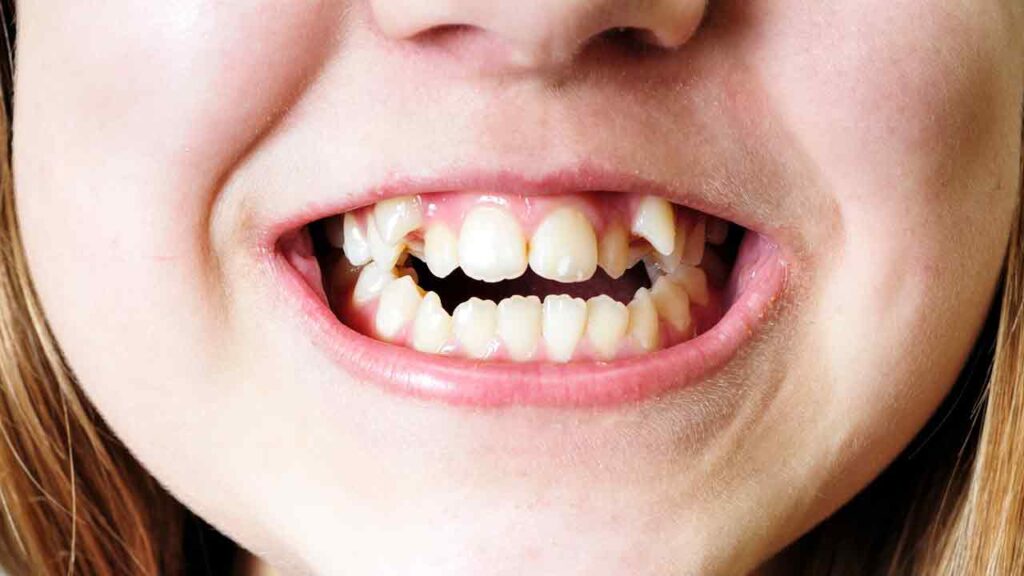

هر شخص معمولا بیست دندان شیری دارد و با رشد و رسیدن به سن بلوغ سی و دو دندان دائمی جای آن ها را می گیرند؛ اما برخی از افراد یک یا چند دندان اضافی در فک خود دارند که این دندان ها، هایپردونتیا نام دارند. ارتودنسی دندان اضافه باعث رفع تاثیر منفی بر توانایی های غذا خوردن و تکلم می شود.

این دندان ها در جلو و یا پشت دندان شیری یا دندان دائمی رشد می کنند. اگر دندان های اضافه جلوی درآمدن دندان های دائمی کودک را بگیرند دندانپزشک باید آن دندان اضافه را خارج کند و ایجاد ظاهری نامناسب در دندان های جلویی از مشکلات دندان های اضافه است. برای حل این مشکلات با ارتودنسی و یا کشیدن دندان اضافه در فک بالا و پایین باید هرچه زودتر به یک متخصص ارتودنسی مراجعه کنید. تا انتهای مقاله با مجله ارتودنسی کرج ارتو همراه باشید تا بیش تر با دندان اضافه در فک بالا و پایین آشنا شوید.

این دندان های اضافی می توانند عوارضی از قبیل تاثیر بر ظاهر دندان ها و یا تاثیر منفی بر سلامت دهان و سایر دندان ها می تواند داشته باشد. در شناسایی این مشکل باید عجله کنید تا دچار عوارض ناشی از دندان اضافه در لثه بالا و پایین نشوید.

- غیرطبیعی شدن ظاهر دندان ها

- تغییر شکل دندان ها – دندان های اضافه اکثرا باعث کجی دندان ها یا چرخش و جابجایی دندان ها می شود.